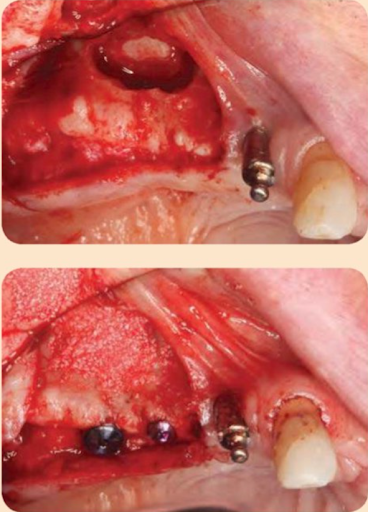

Nếu chiều cao xương còn lại và chất lượng xương tạo ra đủ độ ổn định sơ khởi cho implant, thì có thể đặt implant đồng thời với nâng xoang. Nó được gọi là phương pháp một thì. Khi không đủ chiều cao xương, có thể rất khó để đạt được ổn định sơ khởi của implant, và cần thực hiện phương pháp hai thì. Như một quy tắc chung, cần tối thiểu 3-5 mm chiều cao mào xương ổ để tạo độ ổn định sơ khởi cho implant, nhưng bằng chứng hiện nay trong y văn vẫn còn mâu thuẫn. Hội nghị Đồng thuận về Xoang 1996 đã đưa ra các khuyến nghị sau. Nếu chiều cao xương còn lại là 7-9 mm, thì kỹ thuật đục xương (osteotome) là an toàn và có thể đặt implant đồng thời (Hình dưới đây).

Nếu chiều cao xương còn lại là 4-6 mm, thì kỹ thuật của sổ ngoài kết hợp đặt implant trì hoãn hoặc đồng thời được khuyến nghị. Cuối cùng, nếu chiều cao xương còn lại là 1-3 mm, thì kỹ thuật cửa sổ ngoài kết hợp vật liệu ghép rồi đặt implant trì hoãn là phương án điều trị tốt nhất.